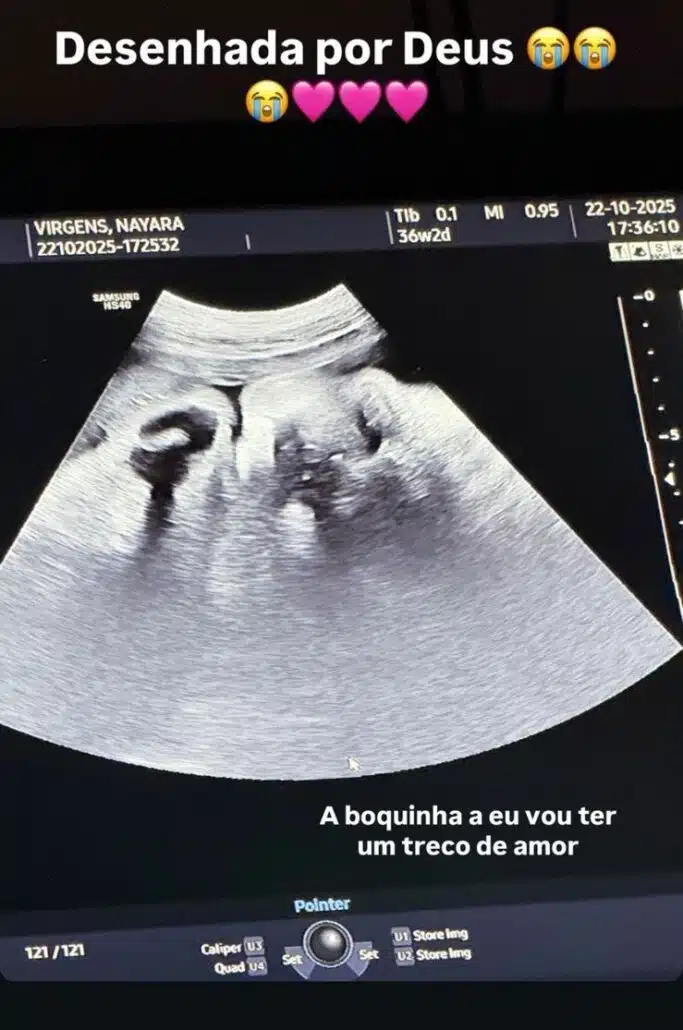

Any disse: “Pra todo mundo que falou que ia nascer hoje, tô indo embora para casa, e grávida!”. Ela também mostrou o ultrassom que fez de sua filha durante a ida para a maternidade. E Any acabou revelando que estava com 36 semanas e 2 dias de gestação. Lembrando que o parto é considerado a termo, ou seja dentro do tempo esperado, entre 37 semanas e 42 semanas de gestação.

Ao mostrar sua bebê no ultrassom, Any Awuada elogiou a bebê dizendo: “Desenhada por Deus! A boquinha! Eu vou ter um treco de amor!”. Ela continuou e explicou o ultrassom: “Gente, vocês viram, essa foto que eu postei, muita gente não consegue entender ultrassom, gente é o rostinho da neném. Vou circular a boquinha para vocês verem!”.

Ela também brincou ao falar da aparência de sua filha. “Achei tão bocudinha! É que ela já tá vindo com preenchimento labial! É para quem pode meus amores! Hahaha! A mini diva já está vindo de preenchimento labial com esse bocão!”.

No ultrassom que Any Awuada acaba de mostrar de sua bebê, ela revelou que no momento está com 36 semanas e 3 dias de gestação. Isto significa que ela engravidou por volta do dia 24 de fevereiro.